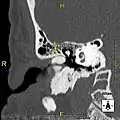

Exostosis in ear canal

The normal ear canal is approximately 7 mm in diameter and has a volume of approximately 0.8 ml (approximately one-sixth of a teaspoon).[5] As the condition progresses, the diameter narrows and can even close completely if untreated, although people generally seek help once the passage has constricted to 0.5–2 mm due to the noticeable hearing impairment. While not necessarily harmful in and of itself, constriction of the ear canal from these growths can trap debris, leading to painful and difficult to treat infections.